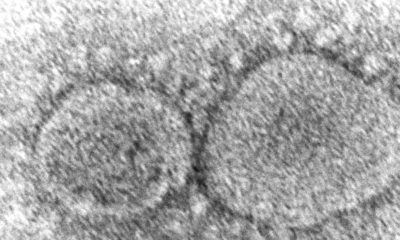

Le virus du SARS-CoV-2 a fait plus d'un million de morts aux Etats-Unis et des millions d'autres dans le monde (archives). (© KEYSTONE/AP CDC/HANNAH A. BULLOCK, AZAIBI TAMIN)

La thèse de la fuite de laboratoire présentée comme la "véritable origine" du Covid-19 est désormais promue dans la version remaniée de la page Internet de la Maison-Blanche sur le virus, dévoilée vendredi. Cette théorie est fortement contestée.

Plus d'un million de personnes sont mortes du Covid-19 aux Etats-Unis et des millions d'autres dans le monde.